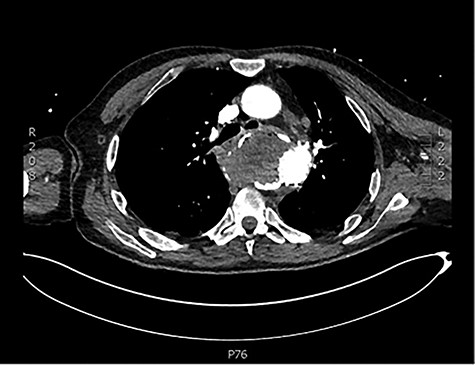

The patient was transferred and stabilized on the critical care unit and discussed with the interventional radiologist. In conjunction with the interventional radiologist and cardiothoracic teams, the patient underwent radiological stenting of the large aneurysm with TEVAR procedure (Figs 2 and 3). Following the procedure, the patient continued to have large volume haematemesis and melaena and underwent repeat oesophago-gastro-duodenoscopy which demonstrated large amount of blood and clot in the distal oesophagus and stomach with continuous brisk active arterial bleeding at approximately 40 cm, which was unsuitable for any endoscopic therapy. Follow-up CT angiography demonstrated satisfactory appearances of the thoracic aortic stent graft with no evidence of endo-leak. The left subclavian artery was well opacified, and the excluded aneurysm sac contained multiple locules of gas suspicious of ongoing fistulous communication with the oesophagus. Following further stabilization, the patient underwent repeat procedure with identification of a tear in the lower third of the oesophagus. The patient was subsequently managed as an oesophageal perforation with no fluid or oral intake and was commenced on peripheral total parenteral nutrition prior to definitive primary repair.

CT scan demonstrating patent stent with no suggestion of endoleak and lack of contrast in aneurysm sac.